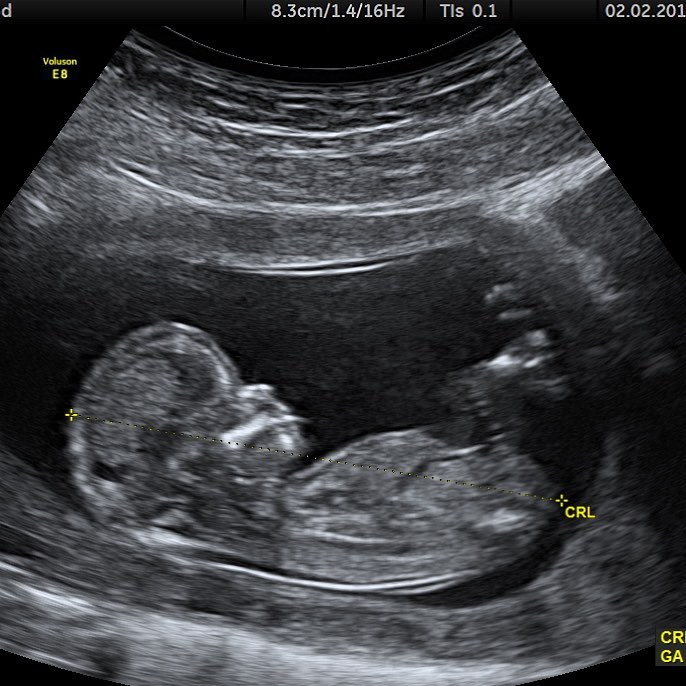

เมื่อวานนี้ นักร้องหนุ่ม “จัสติน บีเบอร์” (Justin Bieber) วัย 25 ปี เผยภาพสุดช็อก เป็นภาพอัลตร้าซาวรน์เด็ก เขาลงภาพนี้ ลงบนอินสตาแกรม สร้างความฮือฮาและความตกใจให้กับแฟนๆ เป็นอย่างมาก แต่บางคนก็อาจจะคิดว่า เขาโพสในวันโกหก วันที่ 1 เมษายน อาจจะเป็นเรื่องที่โกหก และไม่เป็นความจริง แฟนบางคนก็แสดงความยินดี

แต่จริงแล้วๆ เขาโพสอีกภาพ เป็นภาพที่ภรรยาของเขา “เฮลีย์ บีเบอร์” (Hailey Bieber) วัย 22 ปี นั่งจับท้องอยู่บนเตียง และมีสายน้ำเกลือ พร้อมเจ้าหน้าที่อีก 2 คน เขาโพสพร้อมแคปชั่นว่า.. “If U thought it was April fools” ถ้าคุณคิดว่ามันเป็น April fools ซึ่งแคปชั่นนี้ มันทำให้เหมือนเป็นความจริงมากยิ่งขึ้น

ไม่นานหลังจากนั้น จัสติน ก็โพสอีกภาพ เป็นภาพอัลตร้าซาวน์ที่มีรูปลูกสุนัข ซึ่งมันเป็นเรื่องตลกที่เขาสร้างขึ้นมา รูปสุนัขคงหมายถึงสัตว์เลี้ยงของพวกเขา เจ้าออสการ์